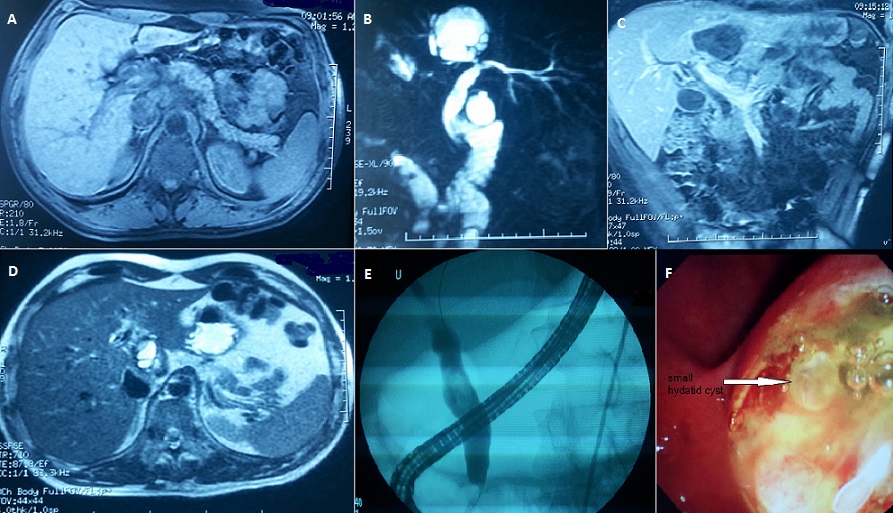

A 49 years old man presented to the emergency department complaining of abdominal pain. He had no medical history and no alcoholism or drug consumption. The pain started 2 days before, accompanied by vomiting and without bowel disturbances. On examination the patient was jaundiced, conscious, cooperative, afebrile, the heart rate was at 110 beats / min, Blood Pressure at 160/82 mmHg, respiratory rate was 25c/min. The pain was epigastric without special irradiation, laboratory data demonstrated a high level of serum lipase: 1199U/L (normal 22-51U/L), total bilirubin 68 mg/l (normal 3-12mg/L), alanine aminotransferase, 183U/L (normal 14-54U/L); aspartate aminotransferase, 105 U/L (normal 15-41 U/L); alkaline phosphatase, 306U/L (normal 32-91U/L); gamma glutamyl trans peptidase 656 U/L (normal 7-50U/L), creatinine, urea levels and Complete blood count were normal . The MRI showed an edematous pancreas (A), a large Hydatid cyst of the left hepatic lobe in contact with the left bile duct (B, C). The common bile duct was dilated (15mm) (D). After pain treatment and correction of hydro electrolytic disturbances, we performed endoscopic retrograde cholangio pancreatography which showed dilated wrung and the absence of opacification of the left hepatic biliary duct (E). Immediately after endoscopic sphincterotomy, hydrated membranes and small vesicles were seen protruding spontaneously through the papillary orifice (F). The patient was discharged from the hospital 10 days later after clinical and biological resolution.